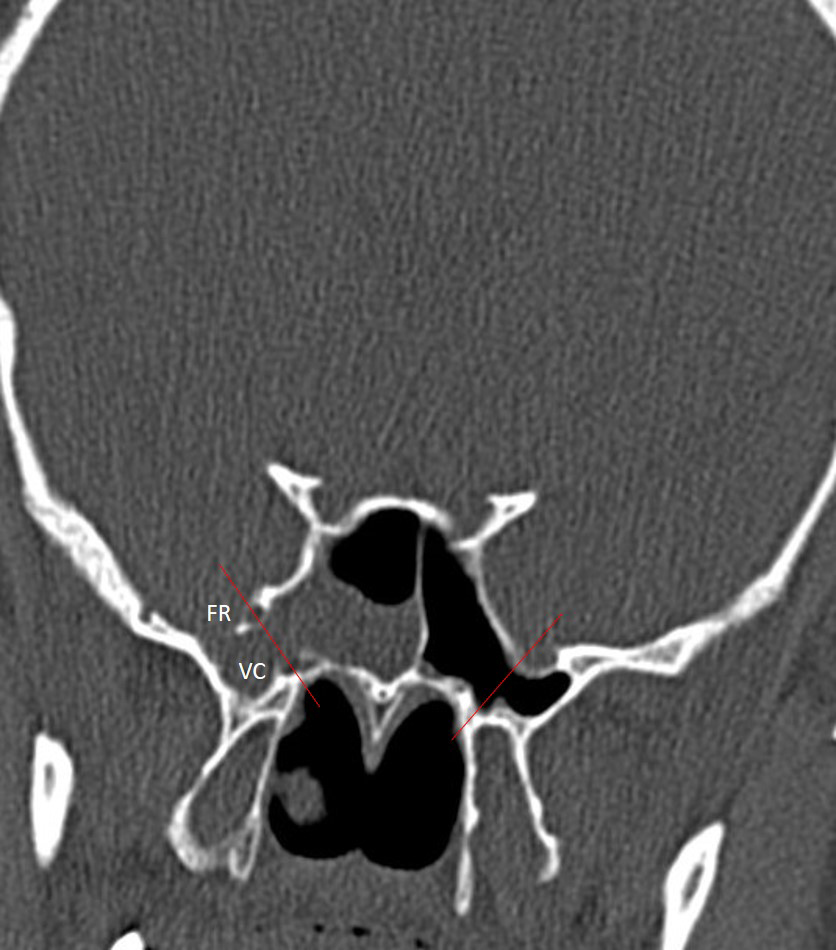

The institutional review board approved this single-center retrospective study. Patients with suspected CSF leakage who underwent MRI with a special protocol between 2012 and 2023 were evaluated. Images of 240 consecutive patients were assessed for CSF leakage by two neuroradiologist with 10 and 3 years of experience. Patients with leakage from sites other than the sphenoid sinus were excluded from the study (n = 220). Six out of 20 patients with a history of trauma or surgery of the sphenoid sinüs or cavernous sinus were also excluded. The remaining 14 patients with sphenoid sinüs CSF leakage formed the study group. Leakage was supported by surgical findings and beta-2 transferrin test. All imaging was performed using 3 Tesla (Verio, Siemens, Erlangen, Germany) or 1.5 Tesla (Aera, Siemens, Erlangen, Germany) MR scanners. The MRI protocol for CSF leakage consisted of T2 weighted fat suppressed coronal plane images with 3 mm slice thickness, T2-weighted sagittal plane SPACE images with 1 mm slice thickness, and CISS coronal plane images with 1 mm slice thickness. All images were evaluated by two radiologist with 4 years of experience in terms of empty sella, enlargement of the Meckel's caves (Figure 1), fluid in the optic nerve sheaths, vertical tortuosity of the optic nerves (Figure 2), arachnoid pits, encephaloceles (Figure 3), and lateral recess pneumatization of the sphenoid sinuses. Lateral recess pneumatization was defined as pneumatization lateral to the line connecting the foramen rotundum and the Vidian canal (Figure 4). The side of the leakage and the other accompanying sites of leakage were noted. The presence of a bony defect was evaluated on CT images (Figure 5).Descriptive statistics were used for data analysis. Continuous variables were presented as mean ± standard deviation [median (minimum?maximum)], and categorical variables were expressed as frequency and percentage.

Figure 4: Coronal CT image of the sphenoid sinus showing the anatomical landmarks used to define lateral recess pneumatization. Lateral recess pneumatization was defined as pneumatization lateral to the line connecting the foramen rotundum (FR) and the Vidian canal (VC). |